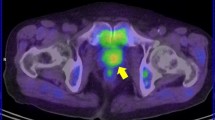

Patients who develop biochemical failure and progressive prostate cancer are difficult to interpret for the effects of androgen status and choline PET results. Studies on these patients looking directly at the influence of ADT on choline uptake are scarce, population groups studied are often inhomogeneous and data on the use of androgen deprivation are not always presented. A good example of a dramatic treatment response resulting from ADT is shown in Fig. 3 [34].

a Maximum intensity projection (MIP) image (left) and fused PET/CT image (right) of [11C]choline PET/CT scan performed after discontinuation of ADT (initial PSA 12.1 ng/ml). Increased [11C]choline uptake in multiple lymph nodes is observed in the MIP image: a large and hot lymph node (SUVmax = 8) is evident in the left iliac chain. b MIP image (left) and fused PET/CT image (right) of [11C]choline PET/CT scan performed 6 months after ADT administration. A complete response is evident. PSA dropped down to 0.01 ng/ml. Reproduced with permission [34]